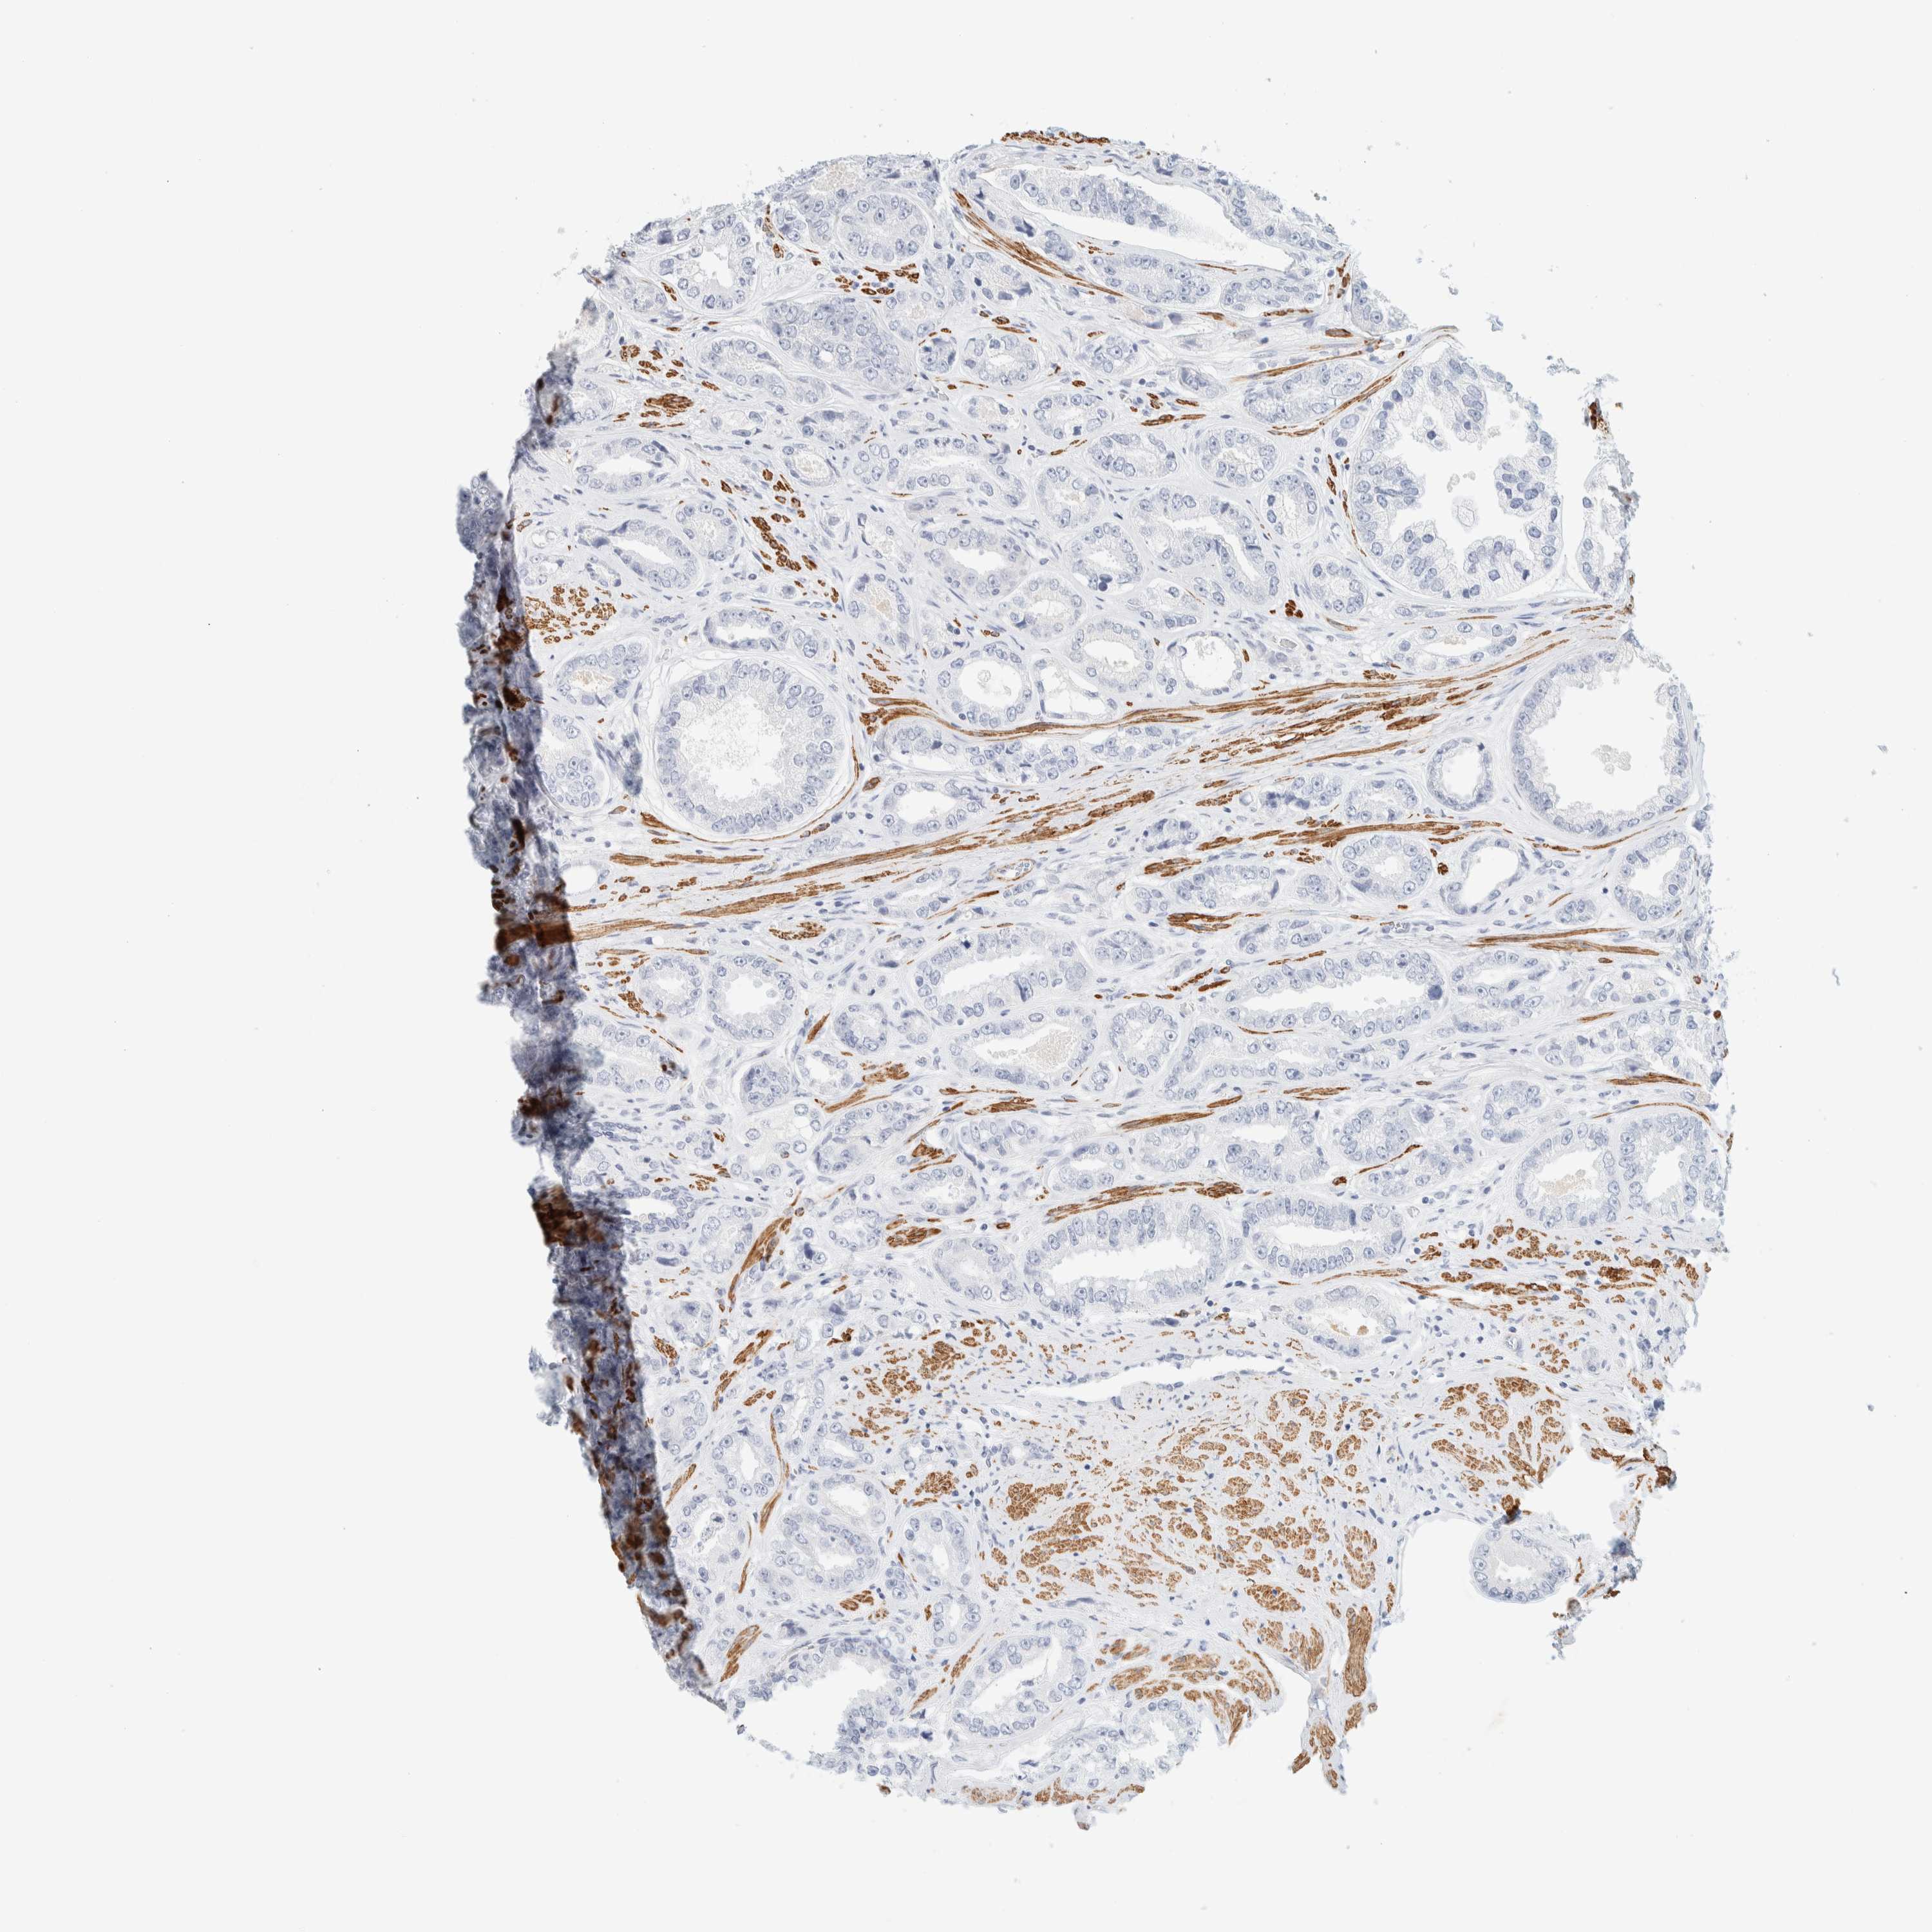

PROSTATE CANCER - Protein expressioni

A mouse-over function shows sample information and annotation data. Click on an image to view it in a full screen mode. Samples can be filtered based on level of antibody staining by selecting one or several of the following categories: high, medium, low and not detected. The assay and annotation is described here.

Note that samples used for immunohistochemistry by the Human Protein Atlas do not correspond to samples in the TCGA dataset.

Antibody stainingi

Antibody staining in the annotated cell types in the current human tissue is reported as not detected, low, medium, or high, based on conventional immunohistochemistry profiling in selected tissues. This score is based on the combination of the staining intensity and fraction of stained cells.

Each image is clickable and will lead to virtual microscopy that enables deeper exploration of all samples and also displays staining intensity scores, fraction scores and subcellular localization as well as patient and tissue information for each sample.

Antibody HPA023861

Antibody HPA026536

Staining

High

Medium

Low

Not detected

Intensity

Strong

Moderate

Weak

Negative

Quantity

>75%

75%-25%

<25%

None

Location

Nuclear

Cytoplasmic/membranous

Cytoplasmic/membranous,nuclear

Adenocarcinoma, High grade

Adenocarcinoma, Low grade